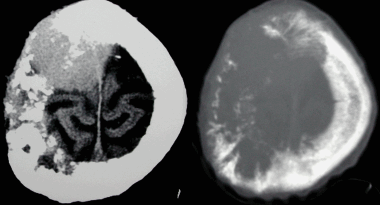

(Справа) МРТ, постконтрастное Т1-ВИ, аксиальный срез: определяется интенсивно и равномерно накапливающее контрастное вещество объемное образование (внутрижелудочковая менингиома). Около 1 % внутричерепных менингиом имеют внутрижелудочковую локализацию; здесь внутри сосудистого сплетения могут сохраняться остатки паутинной мозговой оболочки. (Слева) Бесконтрастная КТ, аксиальный срез: выраженные гиперостоз и кальцификация бляшечной менингиомы, распространяющейся вдоль внутренней компактной пластинки черепа слева.

(Справа) МРТ, Т1-ВИ, аксиальный срез: у этого же пациента определяется характерный гипоинтенсивный сигнал от зоны кальцификации/оссификации. (Слева) КТ с контрастированием, аксиальный срез: справа визуализируются несколько интенсивно накапливающих контраст в немозговых объемных образований с четкими контурами, которые были умеренно гиперденсны на бесконтрастных КТ-изображениях (не представлены).

Псаммоматозная менингиома. КТ-исследование кальцифицированного объемного образования, обнаруженного на рентгеновском снимке. На томограмме, полученной на уровне верхней границы орбит, видна опухоль в области решетчатой пластинки (в области ольфакторной ямки).

Анапластическая менингиома лобной доли. Н а КТ-изображении в режиме мозгового окна и костного окна Хаунсфильда видна крупная внутрикостная менингиома. Обнаруживаемые КТ-феномены неспецифичны и могут включать различные изменения от остеолиза до остеосклероза. Внутрикостные менингиомы составляют менее 1% опухолей костной ткани.